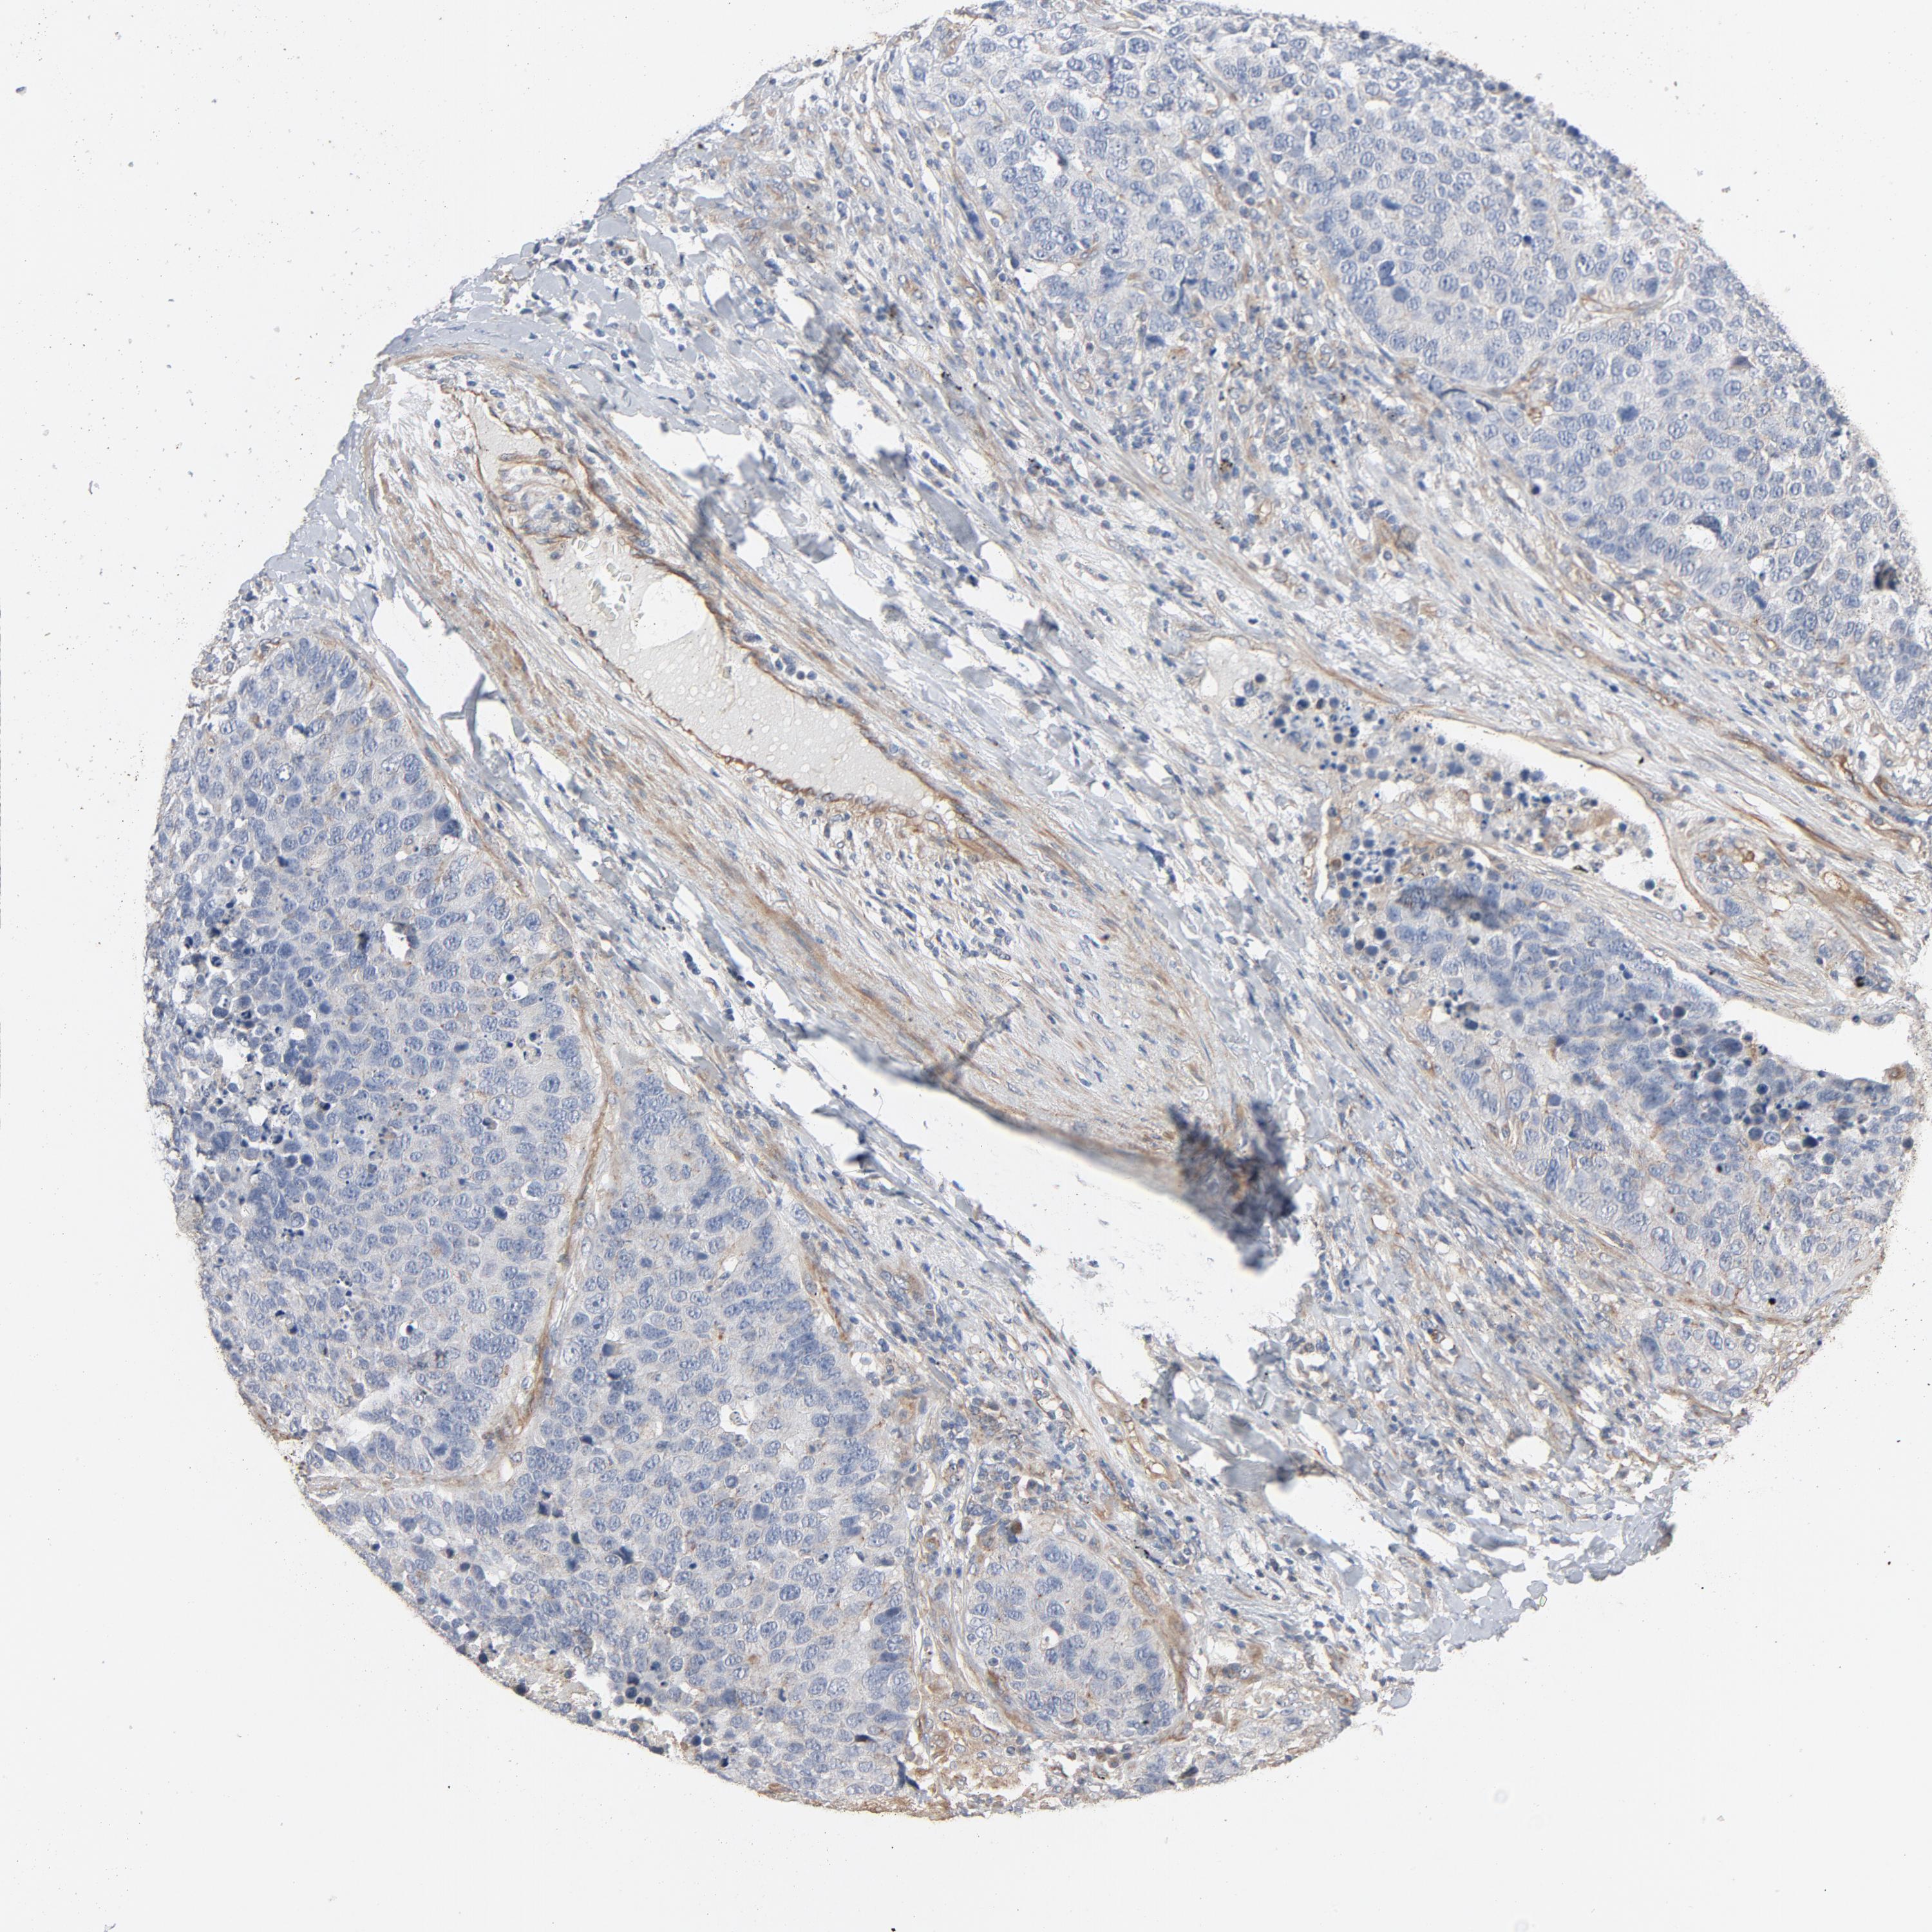

CANCER CARCINOID Show tissue menu

CARCINOID - Protein expressioni

A mouse-over function shows sample information and annotation data. Click on an image to view it in a full screen mode. Samples can be filtered based on level of antibody staining by selecting one or several of the following categories: high, medium, low and not detected. The assay and annotation is described here.

Each image is clickable and will lead to virtual microscopy that enables deeper exploration of all samples and also displays staining intensity scores, fraction scores and subcellular localization as well as patient and tissue information for each sample.

Antibody HPA003747

Carcinoid, malignant, NOS